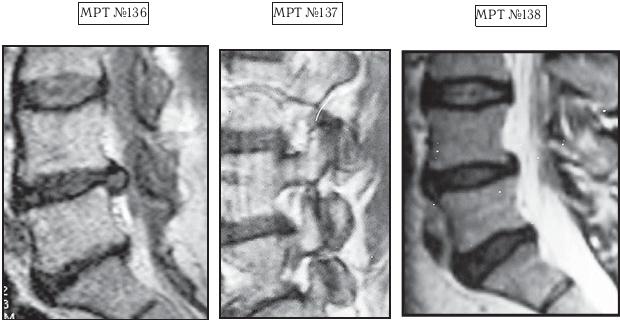

На МРТ № 136 наблюдается состояние поясничного отдела позвоночника после перенесенной ранее операции по удалению грыжи межпозвонкового диска в сегменте LV-SI (практически полное отсутствие межпозвонкового диска), а также грыжа межпозвонкового диска в сегменте LIV-LV, абсолютный стеноз спинномозгового канала, сглаженность физиологического лордоза.

На МРТ № 137 наблюдается выраженный спондилоартроз со смещением суставных поверхностей по отношению друг к другу (нарушение конгруэнтности) вследствие снижения высоты межпозвонковых дисков в сегментах LIV-LV и LV-SI и сглаженности физиологического лордоза.

На МРТ №°138 наблюдается состояние поясничного отдела позвоночника после лечения методом вертеброревитологии: отсутствие грыжи межпозвонкового диска в сегменте LIV-LV, отсутствие стеноза спинномозгового канала, восстановление физиологического лордоза. И самое главное — восстановлен полностью утраченный межпозвонковый диск в сегменте LV-SI!

Так вот, касательно этого уникального случая. Данная женщина была прооперирована по поводу грыжи межпозвонкового диска в сегменте LV-SI. Во время операции, с целью профилактики рецидива, был также удален и сам диск. Это, соответственно, привело к нарушению взаиморасположения (конгруэнтности) суставных поверхностей дугоотростчатых суставов, к «соскальзыванию» позвонка LV кзади (ретроспондилолистезу), что в свою очередь привело к уплощению физиологического лордоза. Таким образом, и без того сниженная выносливость позвоночника, пораженного дегенеративно-дистрофическим процессом, каковым и является остеохондроз, приведший к формированию грыжи, усугубилась ещё больше. А это в свою очередь усугубило биомеханические нарушения и ускорило развитие дегенерации в других сегментах позвоночника. Вследствие данного процесса произошло образование новой грыжи межпозвонкового диска в вышележащем сегменте LIV-LV, расположенном над прооперированным сегментом. Делать вторую операцию пациентка категорически отказалась, тем более что, будучи медиком, она прекрасно осознавала, чем это грозит её здоровью. Собственно это обстоятельство и послужило поводом для посещения данной пациентки моей клиники.

Однако вначале, пожалуй, поясню, почему состояния позвоночника этой женщины значительно усложняло уже имеющиеся теоретические расчёты. Во-первых, во время операции данной пациентке практически полностью удалили межпозвонковый диск. Если внимательно рассмотрите снимок МРТ № 136, то увидите в сегменте LV-SI, лишь незначительное количество оставшихся живых клеток (фрагментов) пульпозного ядра в вентральной части бывшего диска. Во-вторых, гиалиновые пластинки значительно изменены, наблюдается тенденция к сращению смежных тел позвонков. В-третьих, имеется спондилёз и остеофиты в двух сегментах LIV—LV и LV-SI, а также гипертрофия передней связки на этом уровне. В-четвертых, пожалуй, это самый главный аргумент — наличие спондилоартроза, деформация с разрастанием дугоотростчатых суставов на уровне пораженных сегментов (МРТ № 137). А если учесть, что именно дугоотростчатые суставы служат основной опорой в выстраиваемой биомеханической конструкции по методу вертеброревитологии для оптимизации условий к активизации репаративной регенерации, то, естественно, это могло в значительной степени осложнить весь процесс восстановления межпозвонкового диска (я имею в виду в сегменте Ly — Sj) и свести на нет все теоретические расчеты.

Прежде чем приступить к данной работе, я просчитал все возможные риски и удостоверился, что грыжу межпозвонкового диска в сегменте LIV—LV я уберу в любом случае, и даже если бы у меня не получилось восстановить межпозвонковый диск в сегменте LV—SI, то это бы не усугубило здоровье данной пациентки. Должен заметить, что труд был довольно кропотливым, но результаты этой сложной работы оправдали ожидания. Поставленная задача была успешно решена: на практике мне удалось доказать свои же теоретические предположения о возможном восстановлении межпозвонкового диска даже в далеко зашедшей стадии дегенерации, то есть вывести из финальной стадии развития дегенерации межпозвонковый диск и восстановить его до полной функциональной состоятельности. Конечно, основная цель была достигнута, однако сама конструкция, на мой взгляд, была построена не совсем идеально. При восстановлении биомеханики позвоночника и создании условий для восстановления межпозвонковых дисков в сегментах LIV—LV и LV-SI мне пришлось установить позвонок LIV под небольшим углом по отношению к позвонку LV, что было обусловлено значительными изменениями (разрастаниями) дугоотростчатых суставов в данных сегментах. Но несмотря на этот эстетический нюанс, «конструкция» получилась довольно стабильная и функциональная (МРТ № 138).